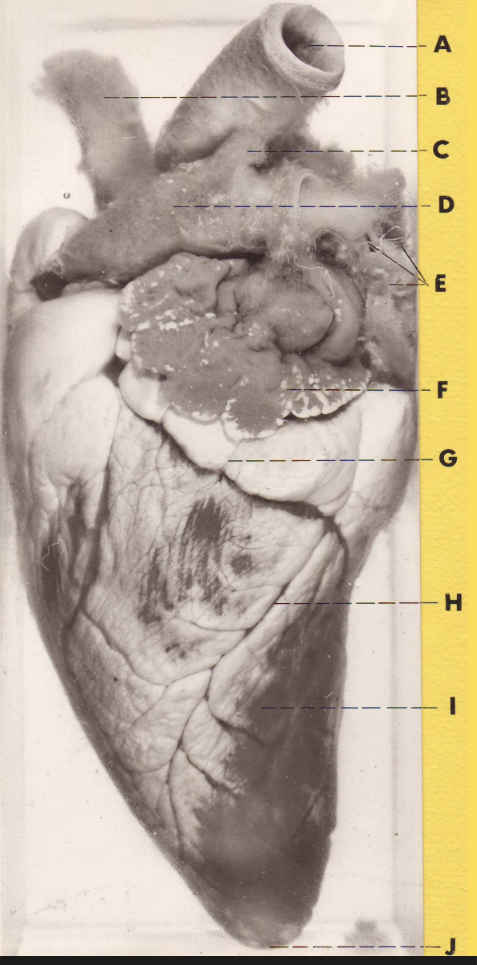

A

(pig heart)

R auricle

B

brachiocephalic trunk

C

L subclavian a

D

aorta

E

ligamentum arteriosus

F

pulmonary trunk

G

L auricle

H

great cardiac v

I

L ventricle

J

apex